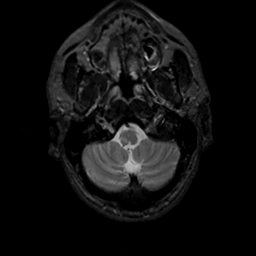

MR Study #7, March 24, 1991 -- Slice #5